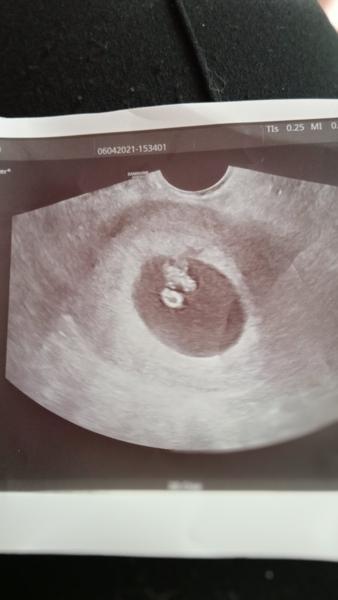

6. dub 2021

@juliemichal ju vše v naprostém pořádku 🤗 i srdíčko ❤️ bije. 🙂 No 7+1tt. Mám být teda 8+3tt, ale mám dlouhé cykly. A vychází to, vím kdy byla ovulace 🙂